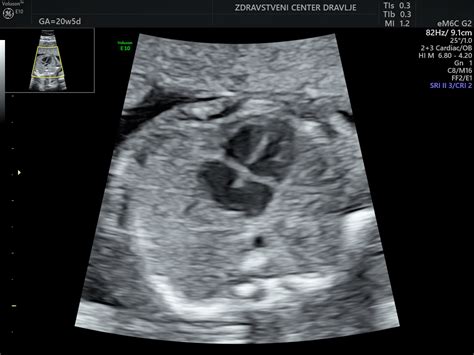

Nuhalna svetlina, morda najbolj poznana kot meritev nuhalne svetline, je neinvazivna ultrazvočna preiskava, ki se izvaja med 11. in 14. tednom nosečnosti. Njen osnovni namen je oceniti debelino prozornega sloja tekočine na zatilju ploda. Povečana debelina nuhalne svetline je lahko povezana z višjim tveganjem za določene kromosomske nepravilnosti, kot so trisomija 21 (Downov sindrom), trisomija 18 (Edwardslov sindrom) in trisomija 13 (Patauov sindrom), pa tudi z nekaterimi drugimi anomalijami ploda, vključno s srčnimi napakami.

Pomembno je poudariti, da sama debelina nuhalne svetline ni dokončna diagnoza, temveč zgolj parameter za izračun verjetnosti. Za natančnejšo oceno tveganja se upoštevajo tudi drugi dejavniki, kot so starost nosečnice, rezultati biokemičnih hormonskih testov (dvojni ali četverni test), ter prisotnost ali odsotnost določenih anatomskih značilnosti ploda, kot je na primer vidnost nosne kosti. Kombinacija teh dejavnikov omogoča izračun individualnega tveganja za posamezno nosečnico.